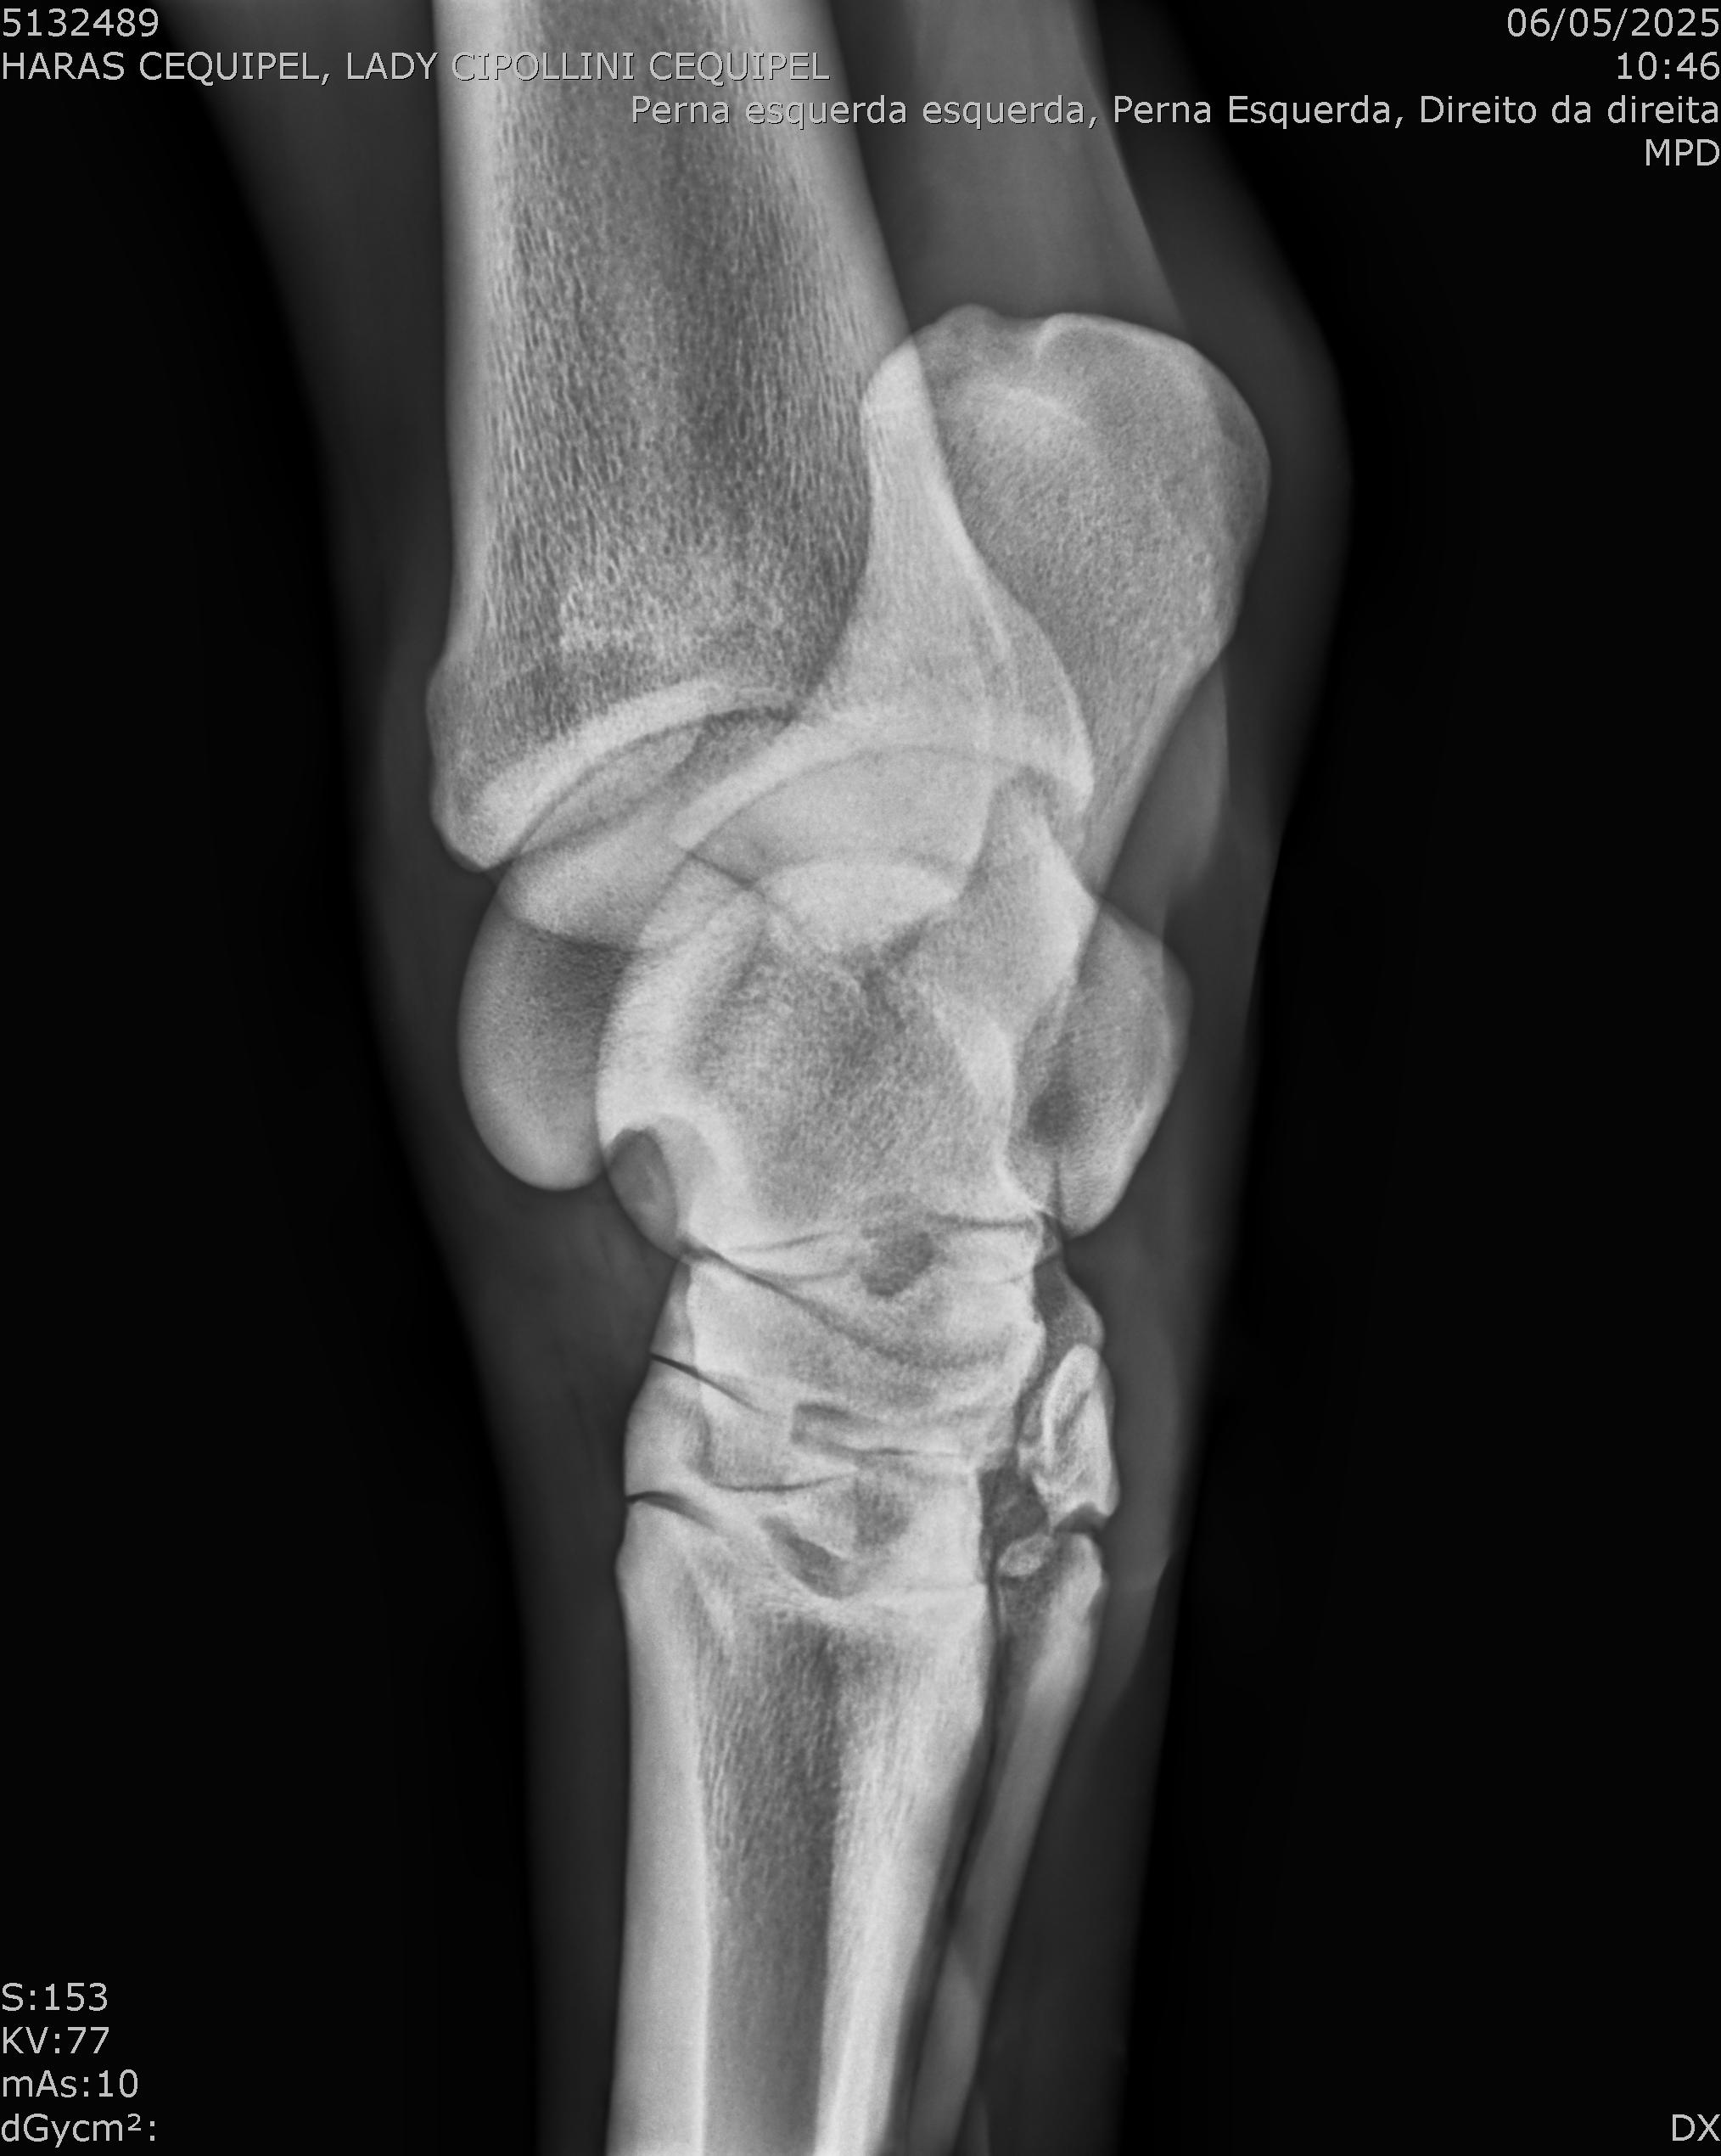

:: RAIOS-X DO LOTE